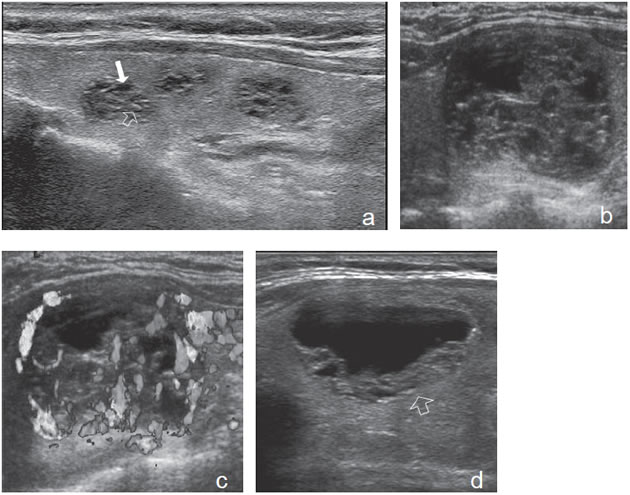

Figura 14. a) Cáncer papilar

hipoecogénico de

bordes irregulares y lobulados,

no encapsulado,

hipovascular, que muestra

un grupo de micro y

macrocalcificaciones centrales

(flecha abierta) con

sombra acústica; b) Nódulo

coloideo avascular

(flecha) marcadamente hipoecogenico.

7. Invasión local y adenopatías

La extensión de la masa fuera de la cápsula, la infiltración de la tráquea o de los músculos pretiroideos es muy sugerente de malignidad (Figura 15a). Asímismo, la presencia de adenopatías con características típicas, debe hacer sospechar que el nódulo tiroideo es maligno. Los cánceres papilares de la tiroides son propensos a dar metástasis precozmente a los linfonodos cervicales y hasta la mitad de todos los pacientes pueden presentar adenopatías concomitantes. En 15% de los pacientes, el único signo de un cáncer tiroideo papilar oculto puede ser la detección de adenopatías. La mayoría de las metástasis ocurren ipsilateralmente al tumor primario en los grupos III y IV de la cadena yugular interna y del grupo VI del compartimiento central. En la ecografía, los linfonodos metastáticos pueden tener una forma redondeada o globular, una arquitectura con elementos sólidos o quísticos, con o sin microcalcificaciones y pérdida del hilio (Figura 15b y c). El “Doppler color” puede demostrar vasos capsulares de distribución caótica en reemplazo de los vasos hiliares normales (Figura 15d). Las adenopatías hiperecogénicas son sospechosas de cáncer papilar (Figura 16a). Los linfonodos normales en algunos grupos como el VI y el VII no se ven ecograficamente, de manera que si se hacen visibles, en el mismo lado del tumor, independiente del tamaño que tengan hay que considerarlos como adenopatías metastásicas (Figura 16b)

Figura 15. a) Cáncer papilar sólido de bordes lobulados (flechas) que muestra una gruesa calcificación central (flecha abierta) y múltiples

microcalcificaciones; b) Adenopatía cervical del grupo IV del mismo paciente (figura 15 a), hiperecogénica, con elementos quísticos (flecha

blanca) y microcalcificaciones agrupadas (flechas negras), típica de cáncer papilar; c) Adenopatías de grupo IV de un cáncer papilar, de

forma redondeada, hiperecogénicas, con pérdida del hilio, una anterior a la arteria carótida común (flecha) y otra lateral a la vena yugular

interna (flecha abierta); d) Corte sagital de la adenopatía lateral de la imagen 15 c), que en “doppler color” muestra vascularización patológica

y pérdida del hilio.